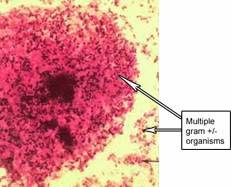

รูปที่ 5 เชื้อแบคทีเรียนานาพันธ์ที่อยู่ในช่องคลอดราวกับสวนสัตว์นี้ ทำให้เกิดภาวะช่องคลอดติดเชื้อได้